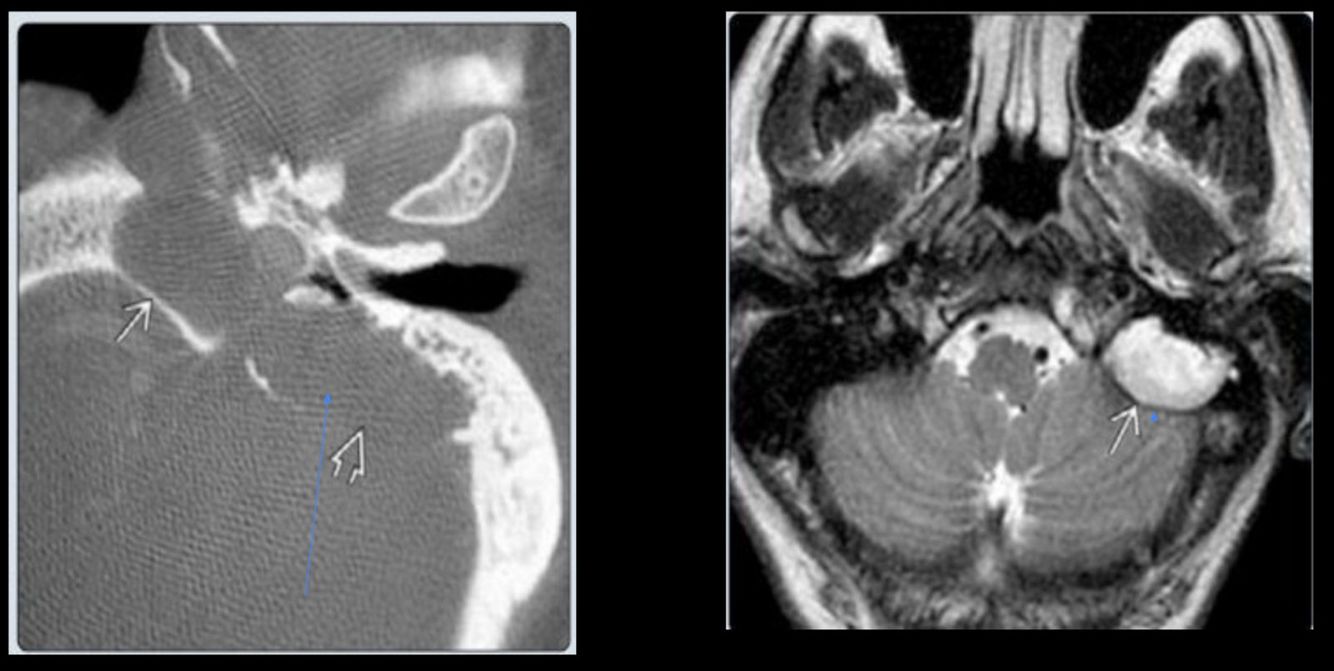

Colesteatoma

El colesteatoma destruye:

¿Cuál es una pista característica del colesteatoma?

Destruye hueso

En la RM del colesteatoma, ¿cómo se observa en T2?

Hiperintensa